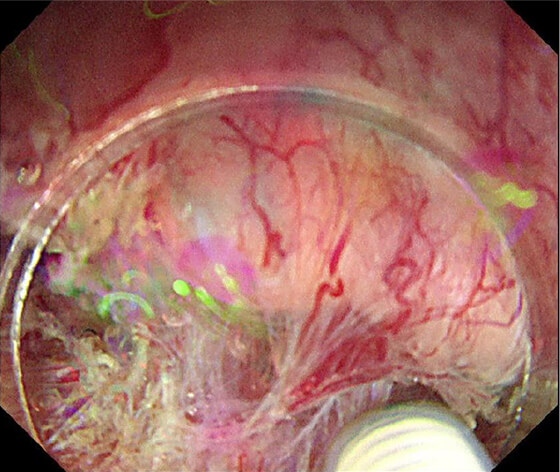

PDT

PDT 5ヶ月後